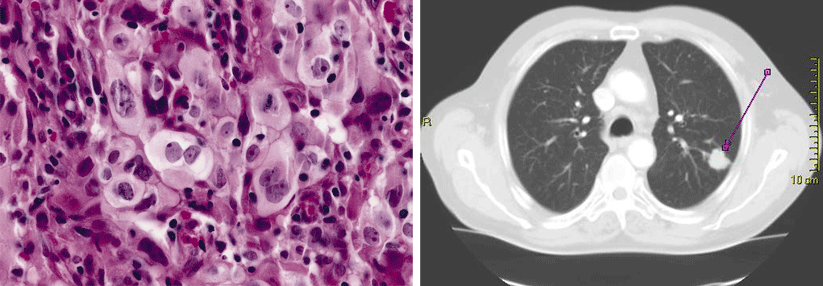

Obwohl es für NSCLC- Mutationen wirksame zielgerichtete Behandlungen gibt, kommt es regelmäßig zu Rezidiven. Obwohl es für NSCLC- Mutationen wirksame zielgerichtete Behandlungen gibt, kommt es regelmäßig zu Rezidiven. © AxelKock – stock.adobe.com

Alterationen in ALK, ROS und RET treten beim NSCLC im niedrigen einstelligen Prozentbereich auf. Zwar gibt es für die Mutationen wirksame zielgerichtete Behandlungen. Allerdings kommt es regelmäßig zu Rezidiven. Zwei Inhibitoren sollen sich dieser Entwicklung entgegenstellen.